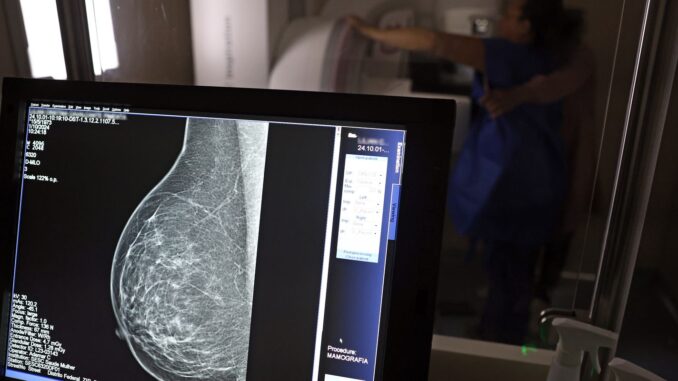

O Ministério da Saúde passou a recomendar a mamografia no SUS para mulheres de 40 a 49 anos sem sinais de câncer de mama. A mudança, anunciada nesta terça-feira (23), altera a orientação anterior, que indicava o exame apenas a partir dos 50 anos.

Segundo a pasta, essa faixa etária responde por 23% dos casos de câncer de mama no país. A detecção precoce aumenta as chances de cura e reduz a mortalidade. A partir de agora, o exame poderá ser solicitado “sob demanda”, após decisão conjunta entre paciente e profissional de saúde, que deverá esclarecer benefícios e possíveis desvantagens do rastreamento.

Dados oficiais mostram que, em 2024, exames realizados em mulheres com menos de 50 anos já representam 30% do total de mamografias feitas pelo Sistema Único de Saúde — mais de 1 milhão de procedimentos.

O ministério também ampliou a faixa etária do rastreamento ativo — quando a mamografia é ofertada a cada dois anos de forma preventiva. O limite, antes fixado em 69 anos, passa para 74. Cerca de 60% dos diagnósticos de câncer de mama concentram-se entre 50 e 74 anos, justificou a pasta.

O Ministério da Saúde estima que, somente neste ano, o SUS tenha realizado cerca de 4 milhões de mamografias de rastreamento e 376,7 mil exames diagnósticos. O câncer de mama permanece o tipo mais comum e o que mais causa mortes entre mulheres brasileiras, com 37 mil novos casos anuais.